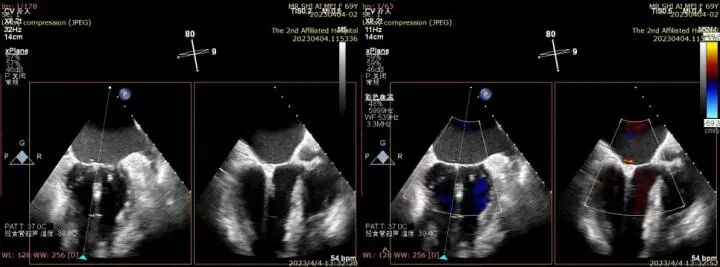

△完全在超声引导下完成二尖瓣夹的定位、瓣叶抓取和二尖瓣夹的释放

△三维超声确认夹合位置理想